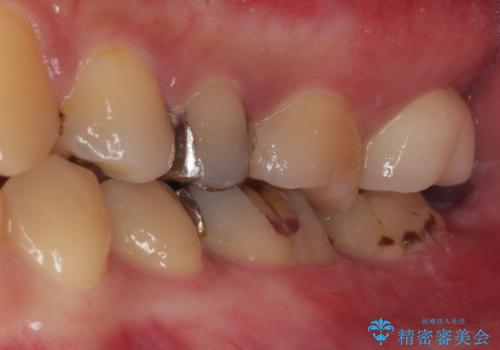

仮歯の状態で1週間ほど過ごしてもらい、歯茎の状態を健全な状態にしてから

歯と歯茎の間に圧排糸と言われる糸を入れてシリコーン印象材にて型どりをしました。

適合もよく、機能的に問題もなく、見た目も満足されていました。

正確な型どりにより再度虫歯になるリスクを低減してくれます。

今後はメンテナンスで通ってもらう予定です。